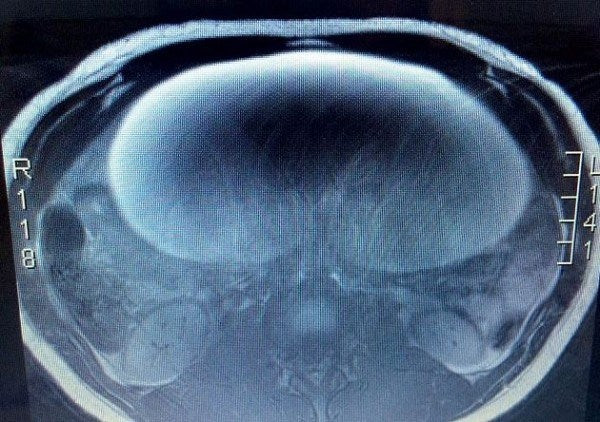

Ο γιατρός υποψιαζόταν ότι ήθελε να κρύψει την εγκυμοσύνη της- Μόλις κατάλαβε τι ήταν σοκαρίστηκε (εικόνες)

Μετά από πολύ δυνατούς πόνους, η πλέον 18χρονη Oli, είχε μεταφερθεί εσπευσμένα στο νοσοκομείο, με πρησμένη την κοιλιά. Όπως φάνηκε τελικά, ο πόνος και το πρήξιμο οφειλόταν σε έναν όγκο...